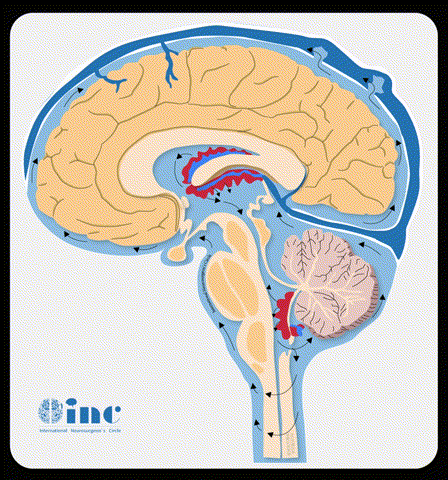

脑动静脉畸形是如何产生的?那这种每10万人中大约发病2人的脑血管病变是如何发生的?当大脑内部发生病变,动脉异常供血,并且有异常回流,在整个脑组织区域形成了局部血管形态结构异常的脑动静脉畸形。动脉和静脉的直接相通而缺乏正常的毛细血管结构是其较主要的特征。

脑室和脑室周围动静脉畸形(AVMs)起源于脑室系统的室管膜表面血管,涉及脉络丛及脑室壁的皮层下结构。脑室病变切除手术不同于实质性的AVMs切除,因为不必对周围的脑组织进行解剖。由于该类型的AVMs缺乏实质性支持,在理论上有很高的出血风险。因此,的外科治疗理念可能是合理的。